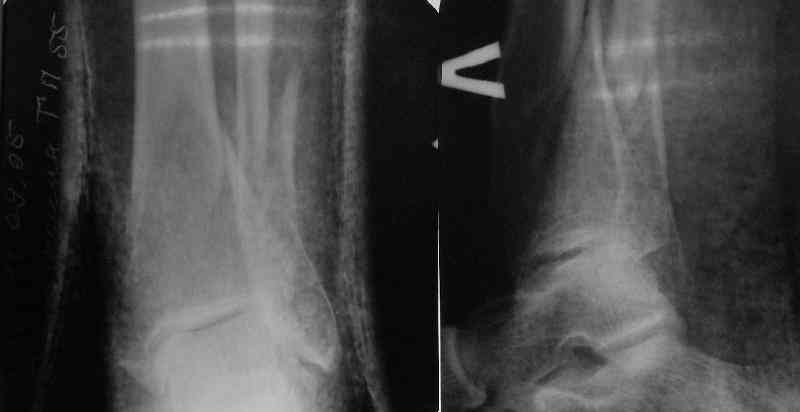

TDVC> Very interesting application, but is the final position in a

TDVC> little distal varus with some fibula distraction?

At least both the ankle mortise and tibial alignment look acceptable, don't they?

TDVC> Would that have been eliminated by fibula plating?

I am just trying to illustrate that prevention of 1)tibial valgus and 2)loss of reduction can be provided without fibular plating. Small changes of conventional nailing techniques allow to maintain reduction of the tibia reliably without adjunctive fibular stabilization.

In delayed cases acute length restoration performed only in the tibia may leave the fibula shortened thus change the mortise. So it is reasonable to restore length of both bones simultaneously by distractor and fix the fibula not with open reduction and plating but just by a single perQ screw. Example attached.